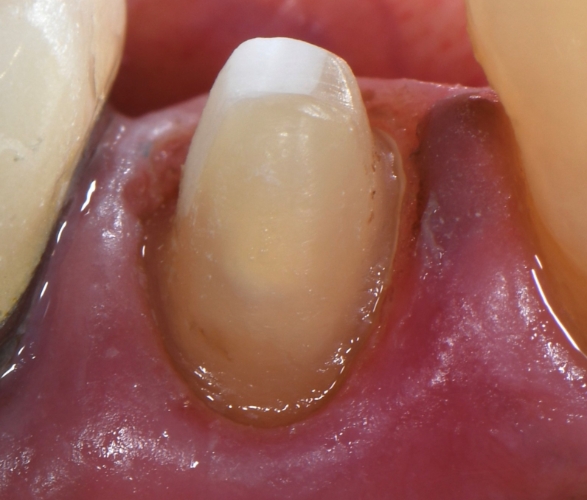

Here is what a tooth looked like underneath an old relatively well “sealed” metal crown

Here is what a tooth looked like underneath a 15 year old fractured onlay – notice the tooth is still clean and sealed from the adhesive resin used for bonding